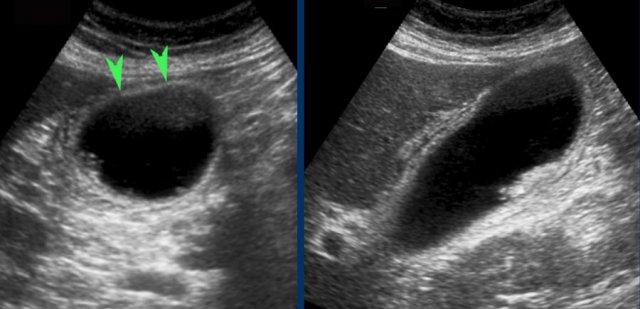

Hình ảnh của một bệnh nhân được nghi ngờ lâm sàng là thủng dạ dày.

CT cho thấy một số sỏi trong túi mật có hình dạng tròn.

Siêu âm bổ sung xác nhận rõ ràng tình trạng phình to túi mật (đầu mũi tên).

Ngay cả trong trường hợp có nhu mô gan xen giữa thành bụng và túi mật, vẫn có thể chứng minh được dấu hiệu “phình to túi mật gián tiếp”.

Hình bên trái cho thấy túi mật duy trì hình dạng tròn, cả trước và trong khi ấn đè, đồng thời phồng lên vào nhu mô gan mềm xen kẽ và thành bụng.

Tương tự, sự vắng mặt của dấu hiệu phình to túi mật cũng có thể được chứng minh, ngay cả khi có nhu mô gan xen giữa, vốn mềm mại khi ấn đè (hình bên phải).